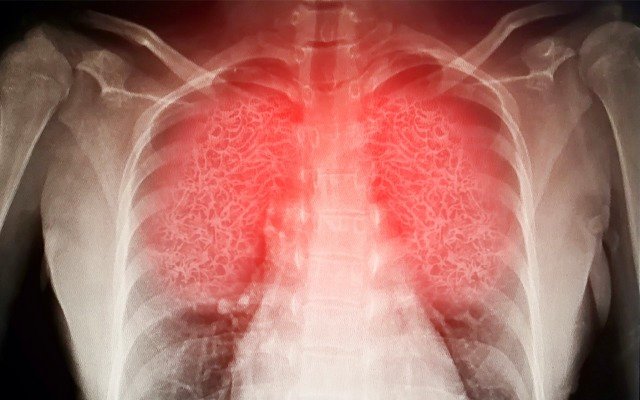

This can lead to “wet lung”, damaging the patient’s lung tissue and can ultimately lead to death, as has been seeing in some hospitalised COVID-19 patients.

SAARDS is characterised by widespread inflammation of the lungs (often referred to as ‘wet lung’ or pneumonia) inhibiting a patient’s ability to oxygenate blood.